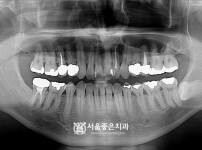

뼈이식 임플란트 2개 - 오스템 임플란트 / 목 신경수술 받으셔서 기다렸다가 임플란트 진행

해당 게시물은 의료법 제56조에 의거하여 로그인 후 열람이 가능합니다.

구분 임플란트